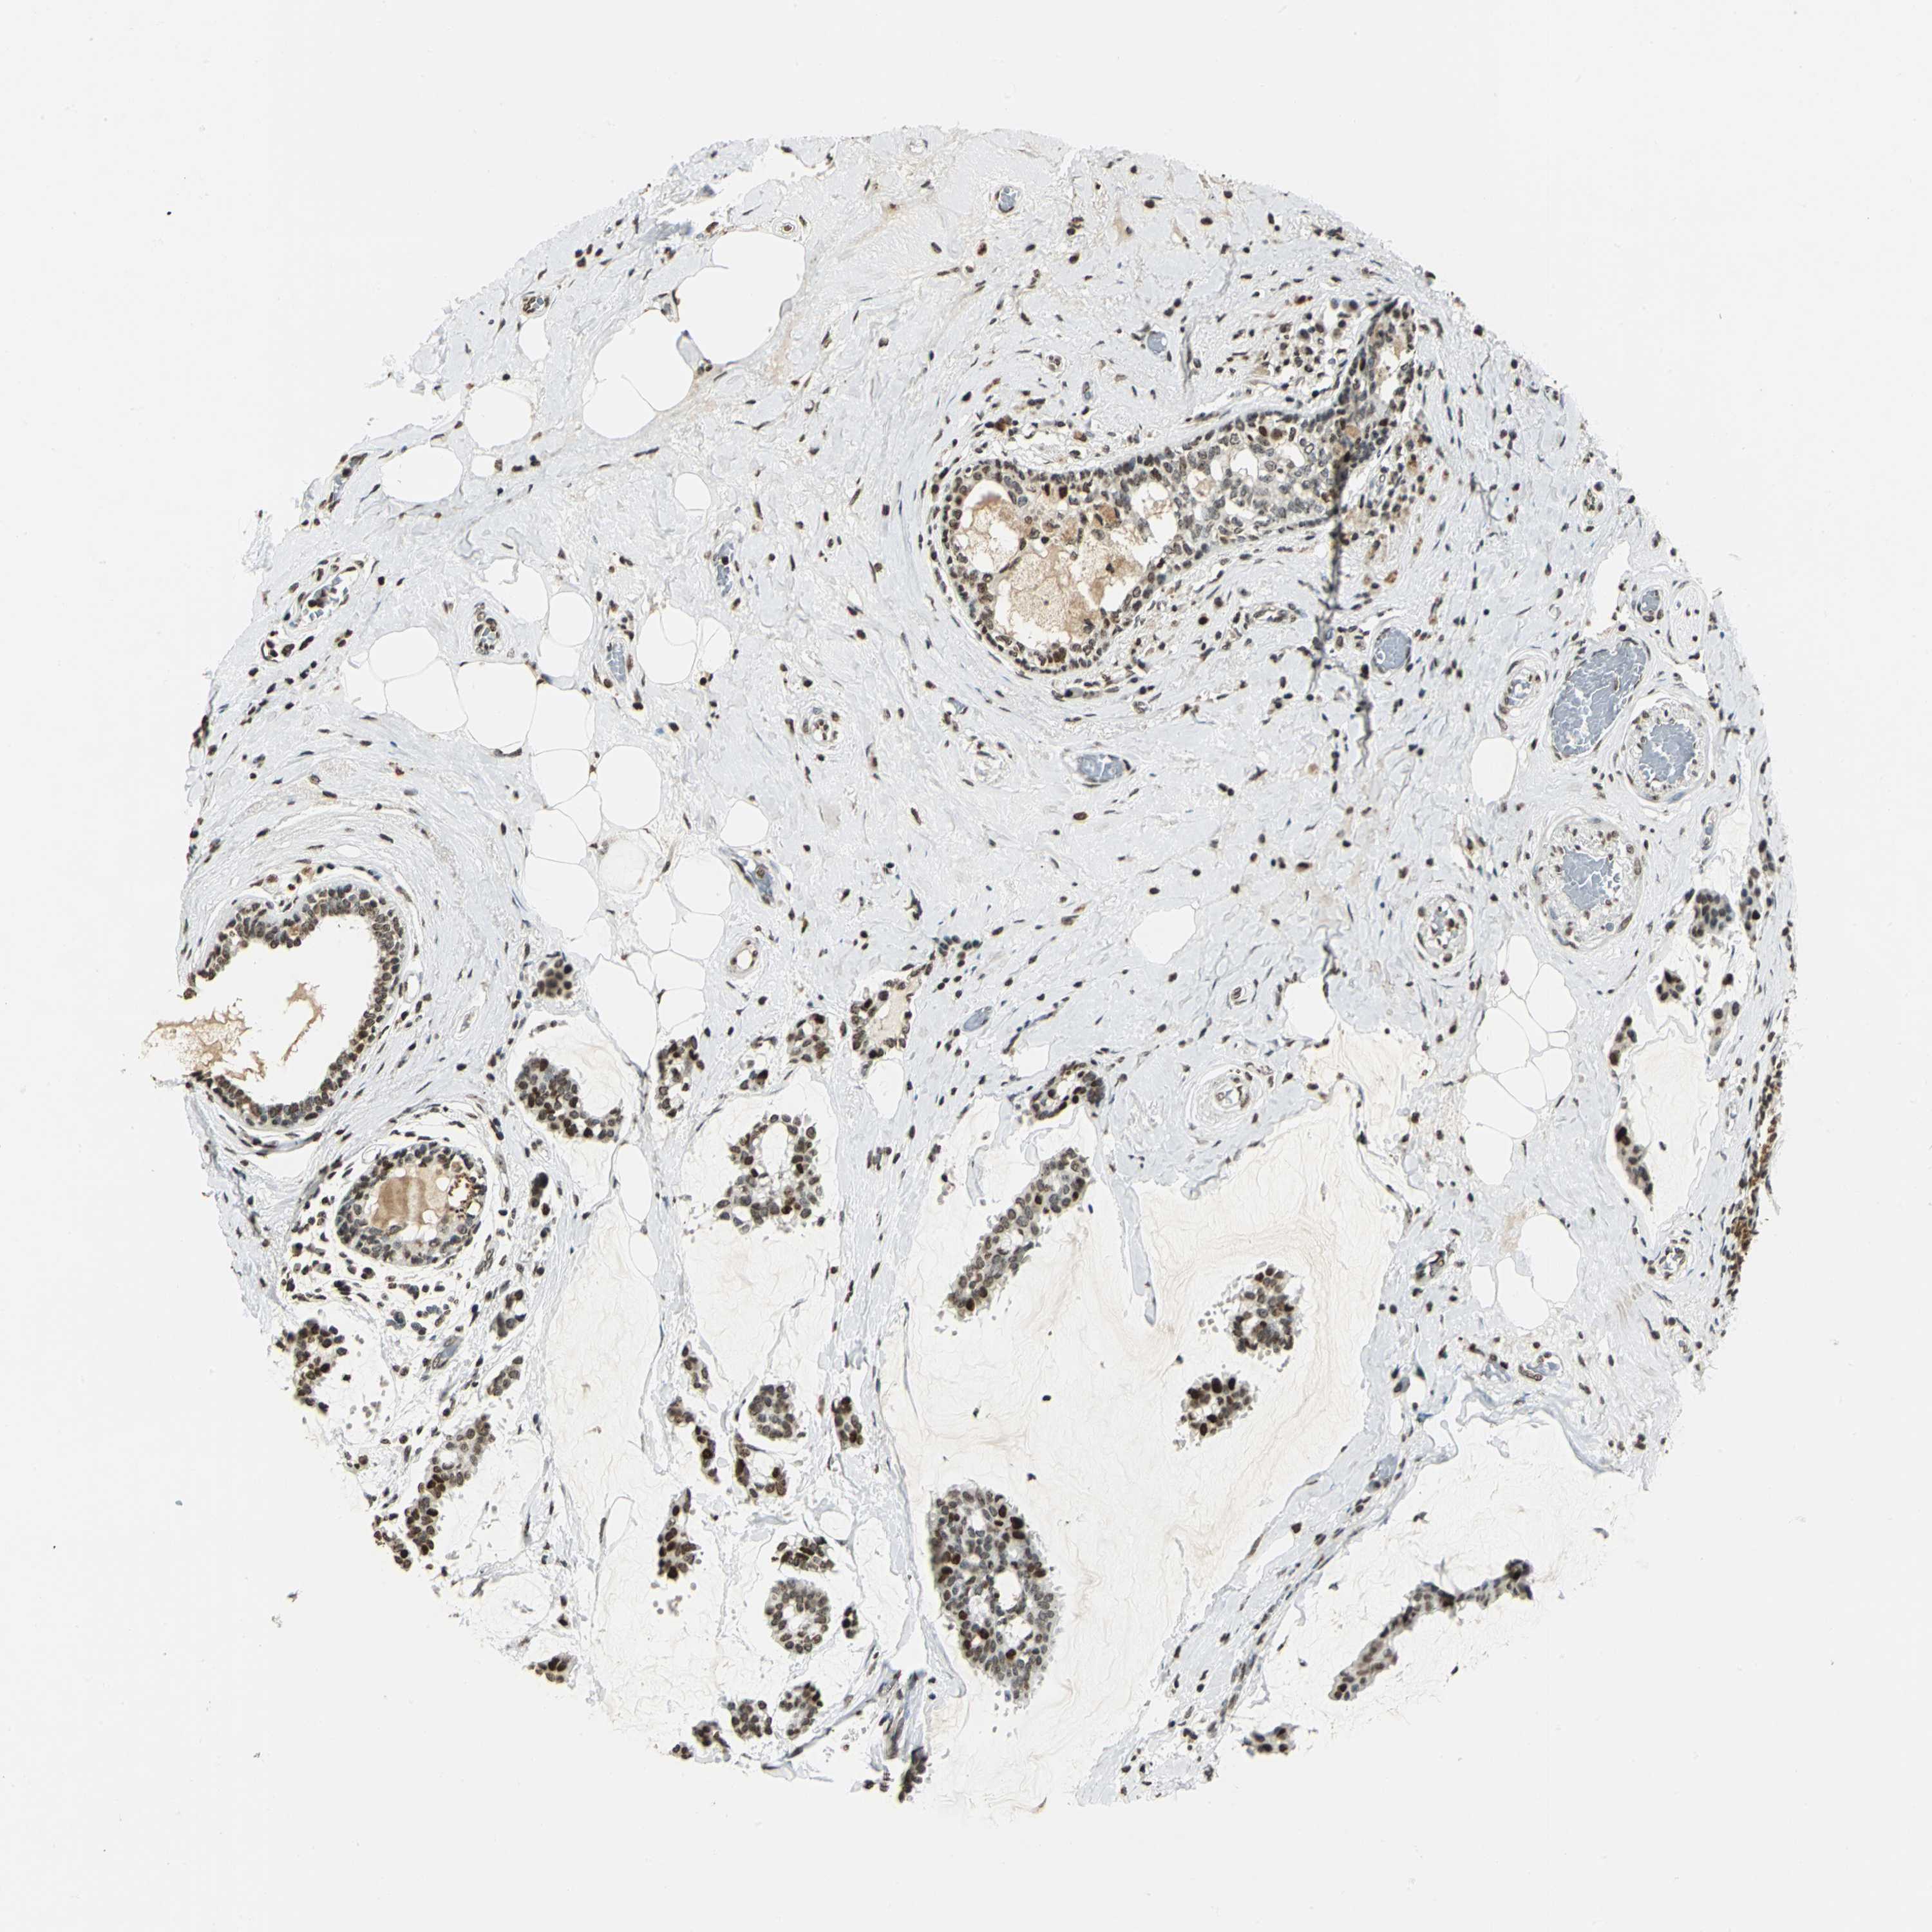

BRCA TCGA BRCA VALIDATION PROTEIN EXPRESSION

ANTIBODIES

AND

VALIDATION